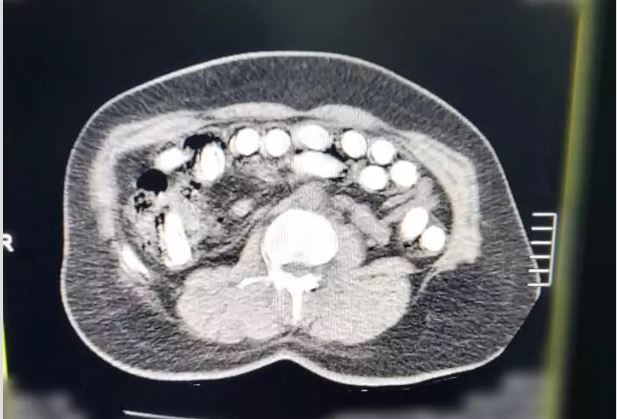

Kayseri’de polis ekiplerince yapılan çalışmalar sonucunda yakalanan 2 şahıstan birinin midesinden ve bağırsağından 88 kapsül şeklinde 974 gram uyuşturucu madde çıktı.

Edinilen bilgiye göre, Kayseri İl Emniyet Müdürlüğü Narkotik Suçlarla Mücadele Şube Müdürlüğü ekipleri tarafından uyuşturucu madde ticareti yaptığı değerlendirilen şahıslarla ilgili çalışma yapıldı. Yapılan çalışmalar neticesinde yakalanan A.G.’nin (36) yapılan iç beden muayenesinde mide ve bağırsak bölümünde 88 kapsül halinde toplam 974.52 gram uyuşturucu madde tespit edildi. Öte yandan, A.A.’nın (34) yapılan üst aramasında; 2,7 gram uyuşturucu ve 76 adet narkotik hap ele geçirildi.